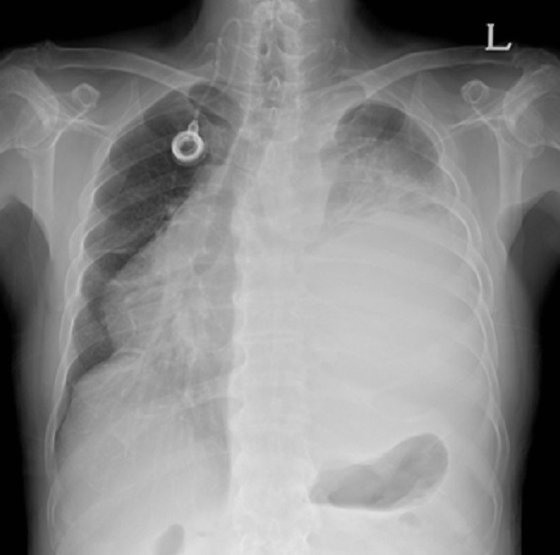

호흡 곤란은 폐암의 증상입니다. 폐암 환자의 약 4분의 1이 호흡곤란 증상을 보이며, 이는 다발성 폐 전이가 양측 증상을 나타내거나 악성 흉막삼출이 폐암과 함께 발생할 때 발생합니다. 폐암은 점차 흉통을 악화시킬 수 있으며, 폐암이 진행됨에 따라 폐암의 크기가 커지거나 그 부위에 물이 차게 되면 호흡이 흉막을 자극하여 호흡곤란과 흉통을 유발할 수 있습니다. 격렬한 작업이나 격렬한 운동을 하지 않았더라도 호흡곤란이 발생하거나 호흡이 불편한 경우 의사의 진찰을 받는 것이 좋습니다.

폐암의 초기증상 중에 흉통이 있습니다. 폐암 환자의 약 1/3이 흉통을 호소합니다. 흉통의 원인은 폐 가장자리에 종양이 형성되어 암세포를 생성하고 흉벽과 흉막에 침착되어 통증을 유발하는 것입니다.

흉통의 원인은 여러 가지가 있을 수 있지만, 오늘날 우리가 다루고 있는 폐암으로 인한 흉통은 경미한 통증보다는 지속적인 따끔거림과 둔한 통증을 동반한다는 점에 유의하시기 바랍니다. 또한 암은 흉막이나 흉벽 대신 갈비뼈로 퍼져 통증을 유발할 수 있습니다. 종양은 주변 조직 세포를 자극할 수 있으므로 계속해서 통증을 유발하는 경우 의사의 진찰을 받는 것이 좋습니다.